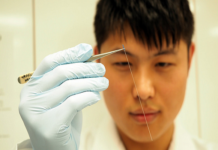

Unlocking Secrets of Brain with Advanced Sensor

Researchers have announced the development of a state-of-the-art sensor that can for the first time detect signalling molecules, called cytokines, which operate in the...